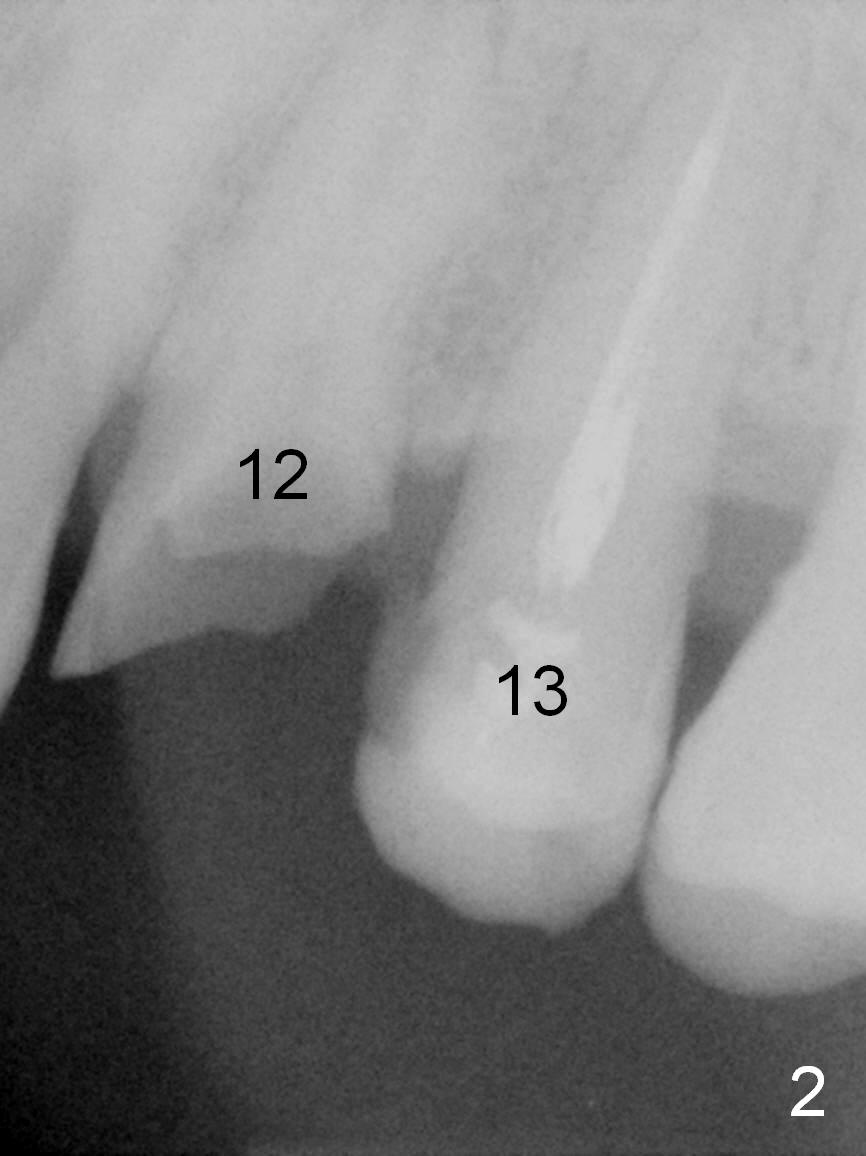

A 45-year-old man presented to our office 8 years ago (Fig.1,2) and got work done somewhere else. He returned yesterday with chief complaint "I might swallow my crowns". Exam shows residual roots at #12,13 (Fig.3,4). The patient has strong jaw bone, suggesting that the bone density is high. Either bone- (Fig.5) or tissue- (Fig.6) level implants will be placed. By time sequence, this case will be assigned to the control group of the antibiotic study. Preop PA does not catch the apices (Fig.3). Take a new one with sensor 1 prior to surgery or panoramus.